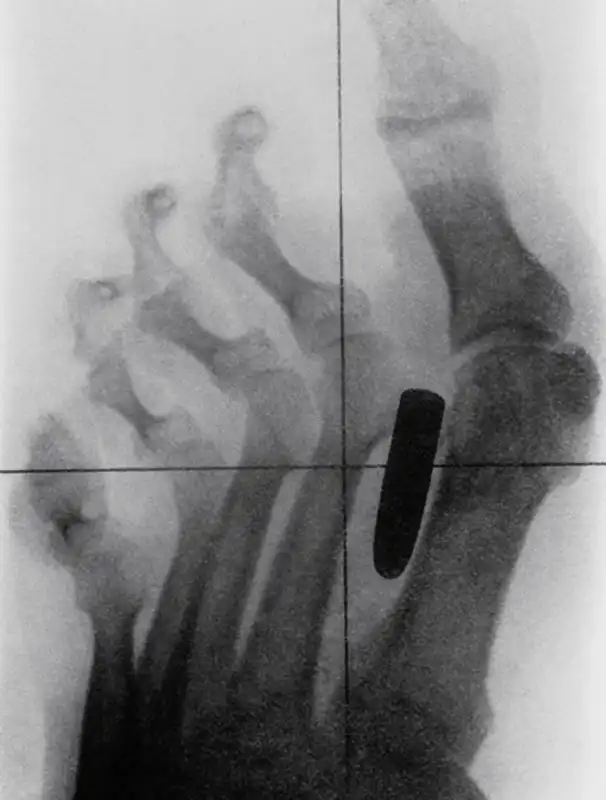

Гвоздь в костях указательного и среднего пальцев взрослого мужчины.